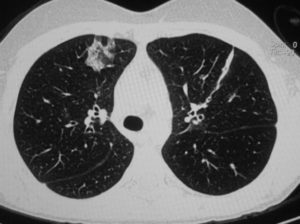

Расшифровка снимков происходит в тот же день. Полученные изображения анализирует врач-рентгенолог, который и выдает заключение. Определить верный диагноз непросто, ведь среди нескольких десятков оттенков черного, серого и белого необходимо вычленить несоответствующий норме и интерпретировать результат. Представим Вашему вниманию несколько фото томографии грудной клетки:

КТ без контраста у пациента с интерстициальным заболеванием легких в анамнезе и трансплантацией правого легкого показывает суженный участок анастомоза правого бронха (красная стрелка). Собственное левое легкое уменьшено в размерах, с признаками бронхоэктазов, бронхиолоэктазов (черная стрелка). Сужение центрального дыхательного пути на выдохе у трансплантированного легкого (синяя стрелка).